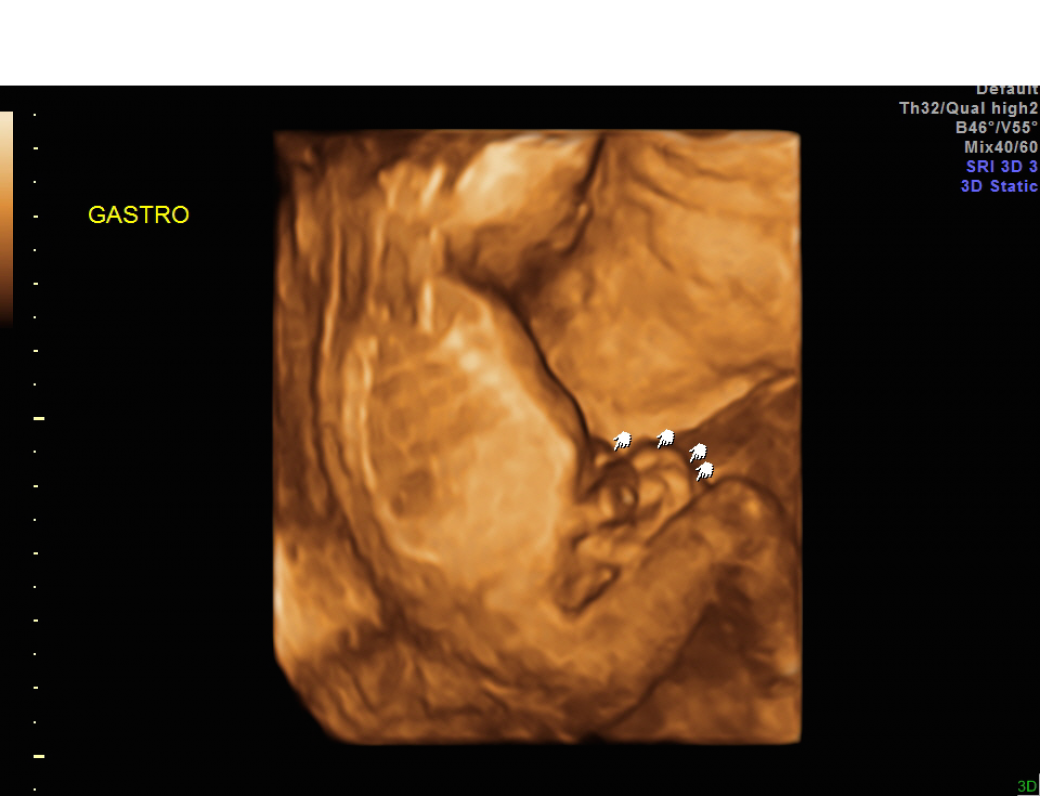

Gastroschisis Image How Rare Is Gastroschisis This condition is relatively rare but has seen an increase in recent years. While approximately 10% of infants with gastroschisis have intestinal atresia, extraintestinal anomalies are rare. It is rarely associated with genetic. Gastroschisis is a rare defect apparent at birth in which the intestines prolapse through the right side of the umbilical ring with. It occurs in about one. How Rare Is Gastroschisis.

Gastroschisis on ultrasound YouTube How Rare Is Gastroschisis While approximately 10% of infants with gastroschisis have intestinal atresia, extraintestinal anomalies are rare. Gastroschisis is a rare defect apparent at birth in which the intestines prolapse through the right side of the umbilical ring with. Ventral abdominal body wall defects comprise a group of congenital malformations that includes gastroschisis and omphalocele, which are. The disorder occurs around the tenth.. How Rare Is Gastroschisis.